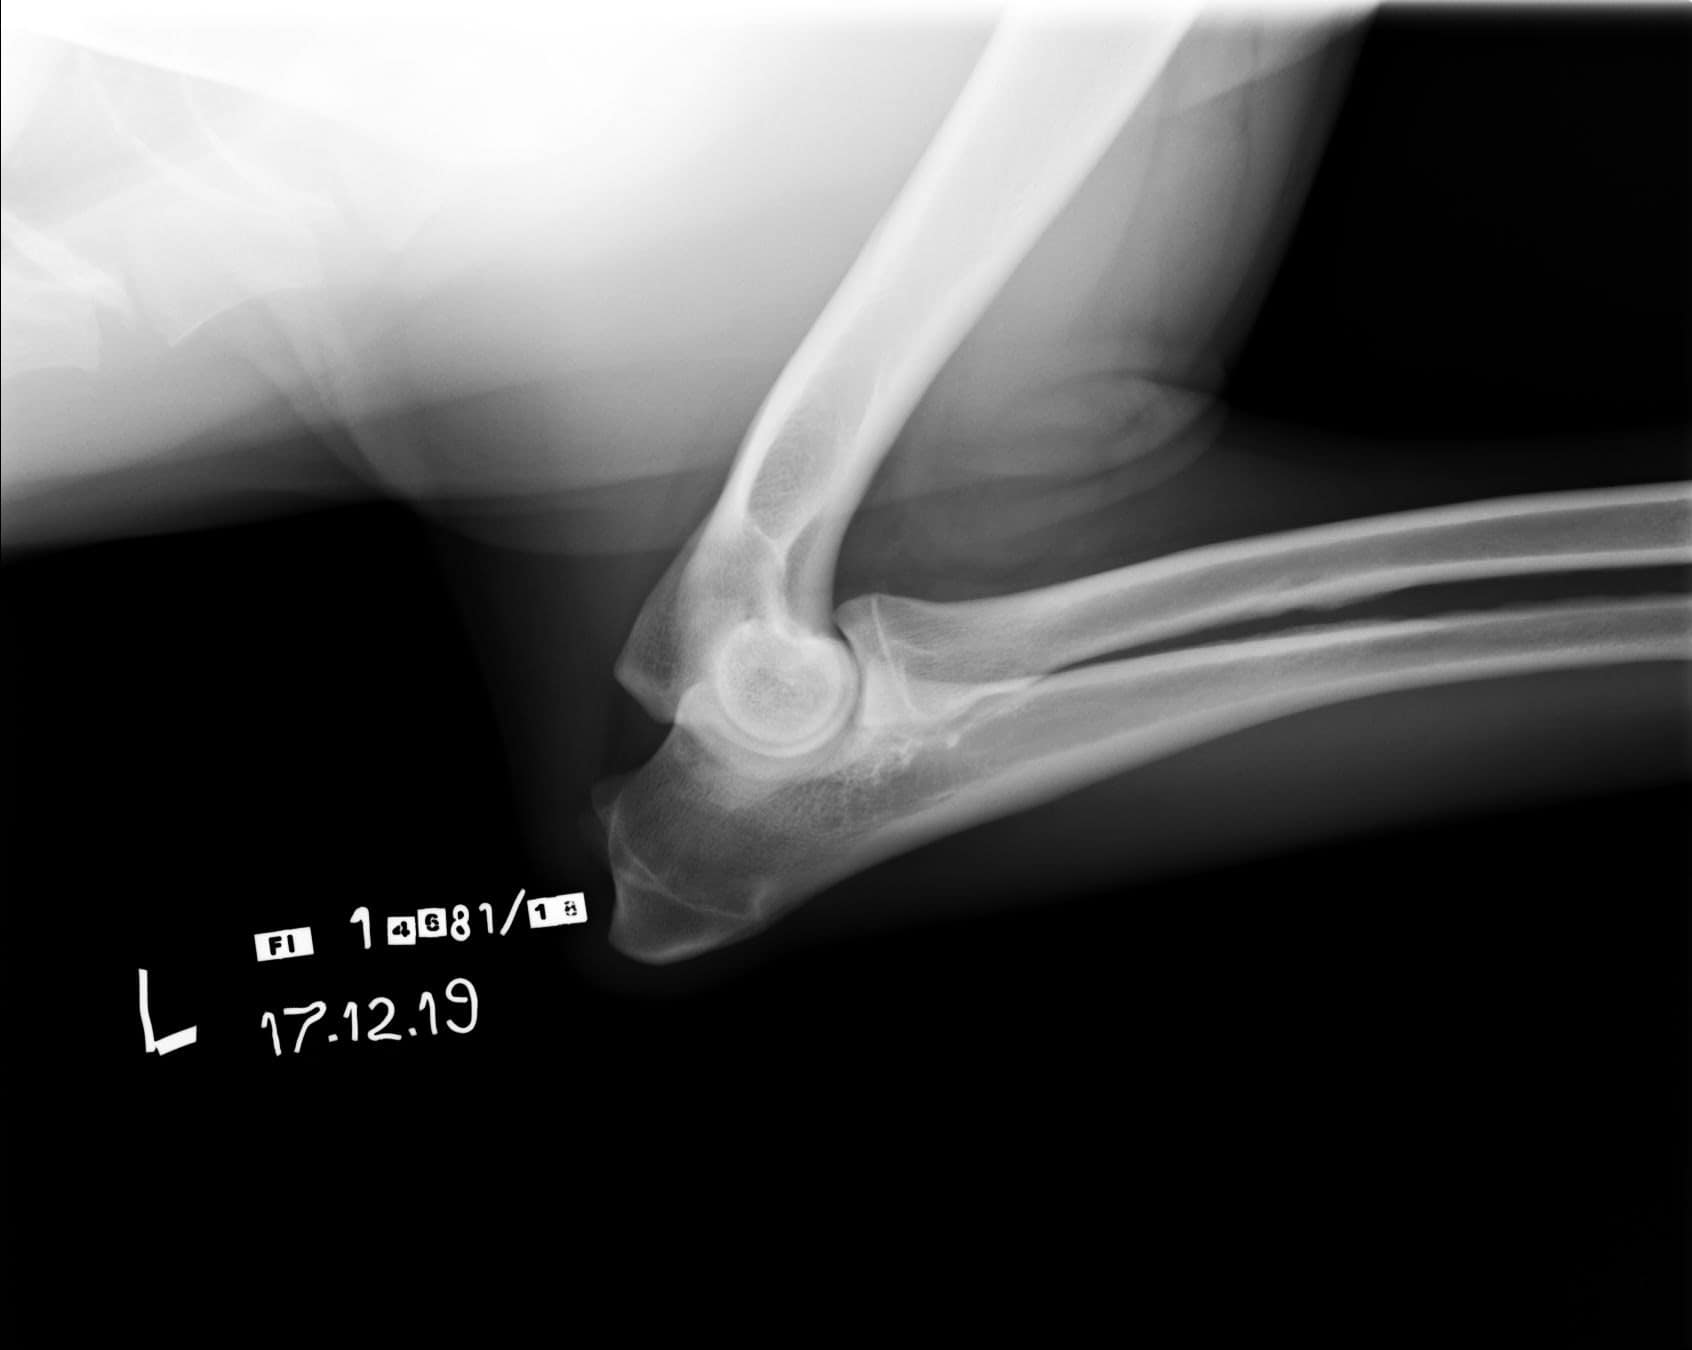

Tähän mennessä Iivo on ollut täysin terve ja Iivo tutkittiin luustoltaan terveeksi joulukuussa 2019. Luonnekuvaukseen (MH, laukausvarma) Iivo osallistui elokuussa 2020.

| Kyynärät: | 0/0 |